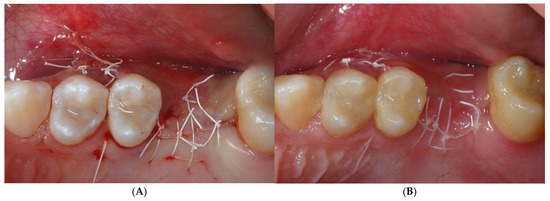

Figure 5.

Tension-free suture with horizontal mattress and single PTFE stitches was obtained (A). Sutures were removed 14 days later (B).

Figure 6.

Radiographic (A) and clinical (B,C) follow-up after a 10-month healing period. Site was re-opened for membrane removal and implant insertion. Smaller paramarginal trapezoidal mucoperiosteal flap, sparing the periodontum of adjacent teeth, was raised (D,E). Membrane was easily removed, and defect appeared completely regenerated (F).